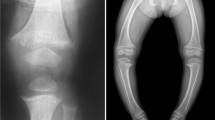

ADHR is characterized by hypophosphatemia due to isolated renal phosphate wasting. Children with ADHR present with skeletal defects including severe bowing of long bones and widening of metaphyseal regions of the bones that is most prominent at costochondral joints. Interestingly, study of a large family cohort with ADHR has revealed evidence of incomplete penetrance, variable onset (pre-pubertal vs. post-pubertal, and spontaneous recovery of renal phosphate reabsorption) (83–85).

XLH (vitamin D resistant rickets) is the most common inherited phosphate wasting disorder with a prevalence of 1/20,000. The defective gene is on the X-chromosome, but female carriers are affected so that it is an X-linked dominant disorder. It frequently becomes manifest during late infancy when the child begins walking. The patient develops skeletal deformities that primarily include bowing of the long bones and widening of the metaphyseal region. The latter is most common at costochondral junctions (rachitic rosary). These deformities are associated with diminished growth velocity, often resulting in short stature. Later in life patients show osteomalacia, enthesopathy (calcified ligaments and teno-osseous junctions), degenerative joint disease, and continued dental disease in particular tooth decay and dental abscesses.

Treatment Strategies for XLH, ADHR, ARHP: Treatment for the above hypophosphatemic conditions depends on the underlying genetic defect. Those disorders caused by genetic mutations associated with low or inappropriately normal 1,25(OH)2D3 levels (as a consequence of elevated FGF-23 that suppresses the renal 25-hydroxyvitamin D 1α-hydroxylase activity) are generally treated with oral phosphate and oral 1,25(OH)2D3. This includes XLH, ADHR, and ARHP. Elemental phosphorus (as Neutra-phos or Neutra-phos K) is administered several times daily. Since the oral phosphate leads to the development of secondary hyperparathyroidism, 1,25(OH)2D3 (available as calcitriol in capsular form or liquid) is also given. Therapy with 1,25(OH)2D3 is adjusted to avoid the development of hypercalcemia and hypercalciuria, yet to maximize the suppression of PTH synthesis and secretion. The therapeutic goal is to maintain serum calcium and PTH levels within the normal range, to improve alkaline phosphatase activity, and to prevent the development of increased calcium excretion. Phosphate therapy in some cases is limited by the development of diarrhea and abdominal discomfort. A renal ultrasound should be performed before treatment and subsequently at 1–2 year intervals. Radiographs of the knees and over the hand/wrist should be performed before treatment and subsequently at yearly intervals.